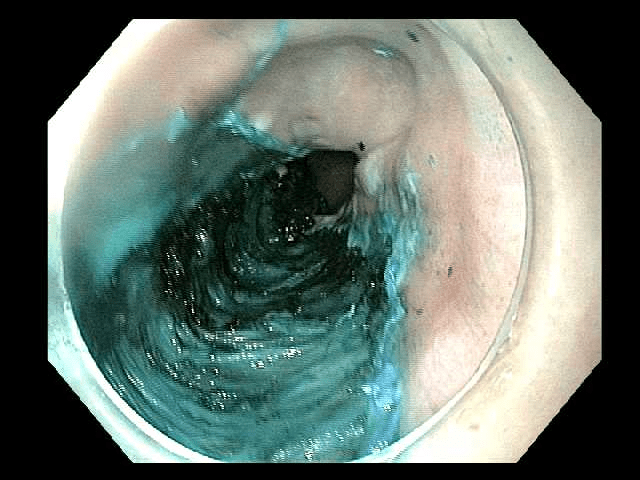

Initial circumferential incisionInitial circumferential incision

This case (Figures 1-5) illustrates endoscopic resection of an early squamous cell esophageal cancer from the mid-esophagus. The patient presented with non-cardiac chest pain, which was thought to be unrelated to this early stage neoplasm. The ESD procedure removed the lesion with clear lateral and deep margins. The resection specimen measured 2.5 x 1.9 x 0.4 cm.